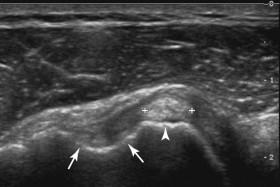

Partial-thickness tears refer to tears that do not extend all the way from the deep to the superficial surface of the cuff. They can involve the deep surface, the superficial surface, or the internal aspect of the cuff. However, the majority arise from the deep surface. The sonographic appearance of a partial-thickness tear consists of a hypoechoic defect that remains visible despite changes in the orientation of the transducer. In many cases there is also a bright reflector associated with the hypoechoic area ( Fig. 11-10 ). As with full-thickness tears, the underlying bony cortex is usually irregular. Unlike full-thickness tears, partial-thickness tears are not associated with contour changes and do not compress with transducer pressure unless they are very extensive. In this situation it can be difficult to distinguish them from a nonretracted full-thickness tear ( e-Fig. 11-6 and ). Both are usually treated with surgery, and therefore the distinction is not critical. Partial tears may also be associated with abnormal internal motion when the transducer is rocked back and forth in the longitudinal plane ( ). Partial-thickness tears must be distinguished from tendon anisotropy, which normally causes the deep surface of the supraspinatus insertion to appear hypoechoic. Tendon anisotropy usually will become more echogenic when the transducer is angled upward, whereas partial tears will not change. Tendon anisotropy is usually poorly marginated, whereas partial tears are better marginated. Finally, tendon anisotropy is usually entirely hypoechoic, whereas partial tears often have at least a small hyperechoic component.

F igure 11-10, Partial-thickness rotator cuff tears in different patients. A, Longitudinal view shows a well-defined heterogeneous but predominantly hypoechoic defect (cursors) along the deep surface of the rotator cuff insertion. The superficial contour is normal. B, Longitudinal view shows a relatively well-defined hypoechoic defect (cursors) along the deep insertion of the rotator cuff. There is also an associated linear, hyperechoic component. Slight underlying bony pitting is also apparent (arrows) . C, Longitudinal dual images of the left (LT) and right (RT) rotator cuffs show a small, well-defined hypoechoic defect (cursors) along the deep surface of the left rotator cuff insertion. This is contrasted to the ill-defined hypoechoic region of anisotropy (arrow) on the right.